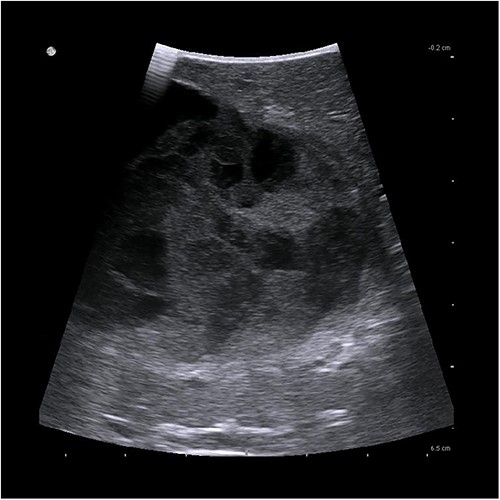

Due to persistent pain, the decision was made to perform a laparoscopic cyst deroofing. In an intraoperatively performed ultra sound (Fig. 3), however, a complex septation was seen so that the decision was made to perform a tru-cut biopsy in order to definitively rule out malignancy.

Intraoperative ultrasonographic localization of the liver cyst.